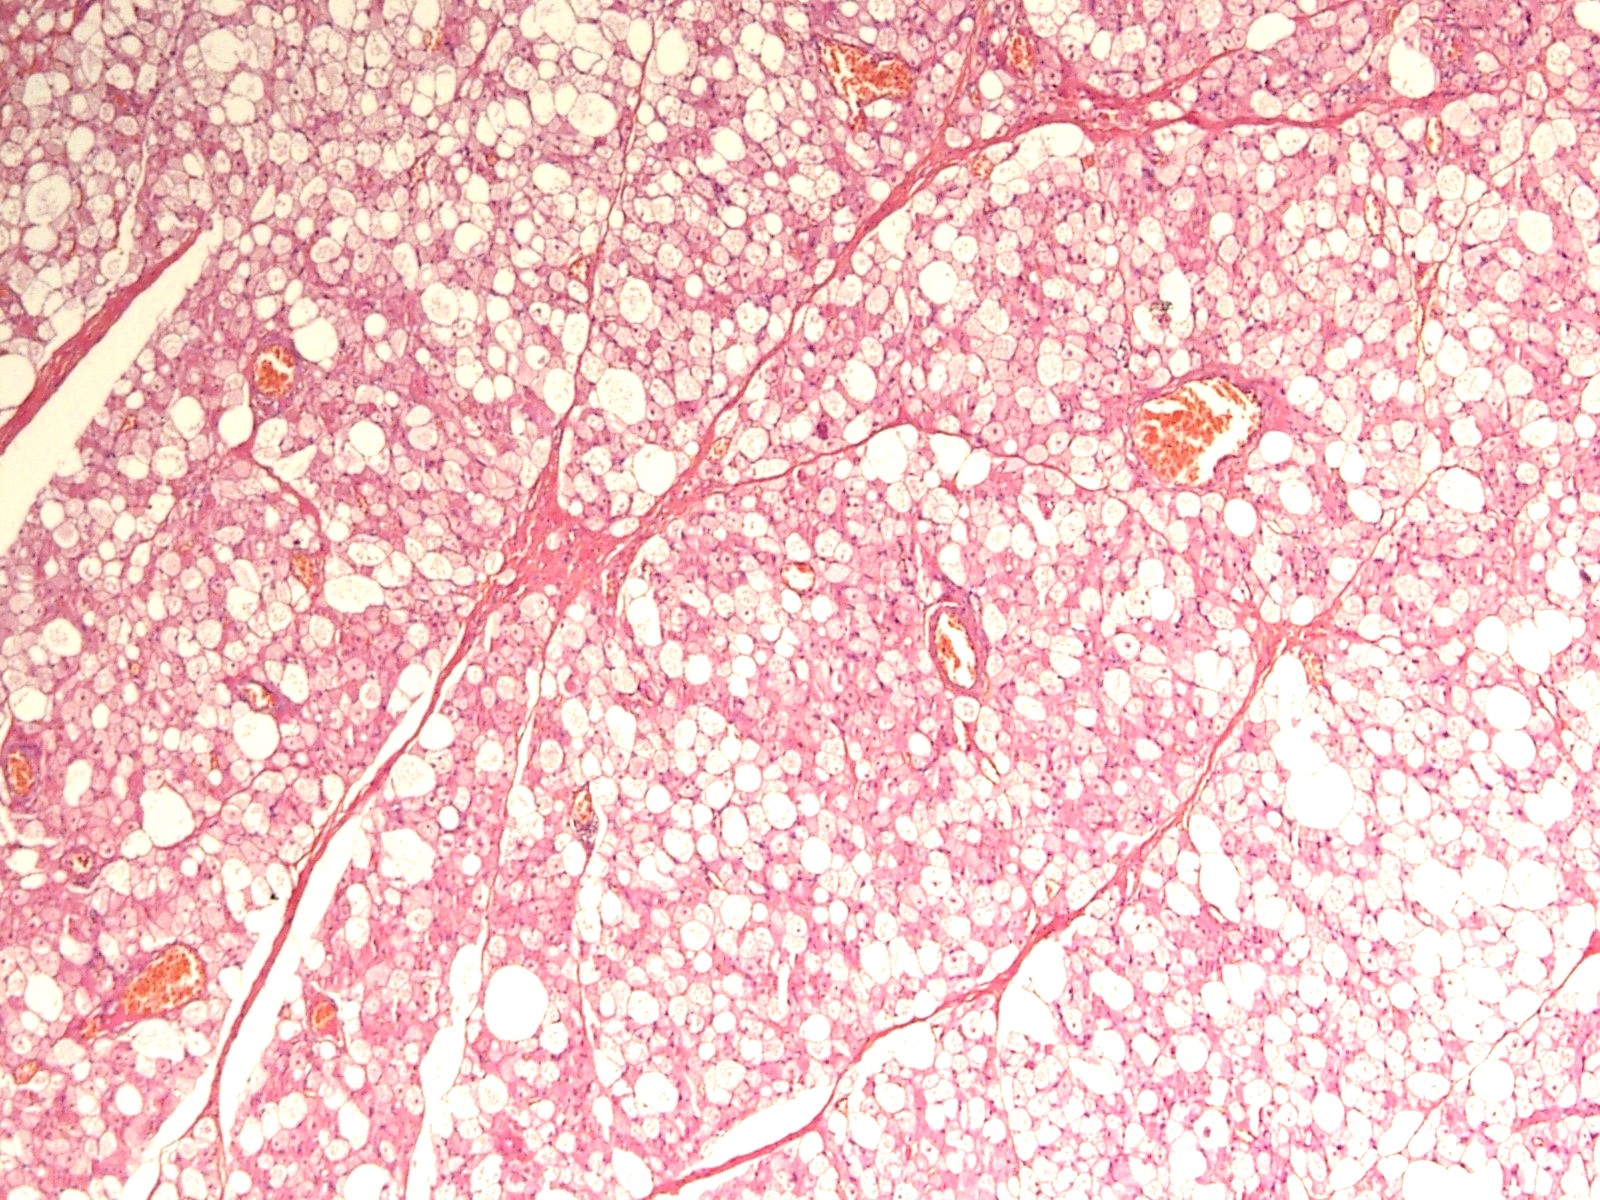

Microscopic (histologic) description

- Neoplastic lesion composed of polygonal brown fat cells with stromal cells in the background (Case Rep Oncol 2017;10:438)

- Large number of pale and eosinophilic brown fat cells with multivacuolated, eosinophilic granular cytoplasm and small central nucleus (about 70%) admixed with variable amount of univacuolated white cells (Case Rep Oncol 2017;10:438, Am J Case Rep 2020;21:e921447, J Comput Assist Tomogr 2019;43:793, J Pathol Transl Med 2017;51:499, Am J Surg Pathol 2018;42:951, Virchows Arch 2021;478:527)

- Multivacuolations resemble lipoblasts

- Morphological variations or subtypes: typical, myxoid (9%), lipoma-like (7%), spindle cell (2%), thick bundles of collagen fibers, presence of mast cells and exclusively containing brown fat cells (Case Rep Oncol 2017;10:438, Am J Case Rep 2020;21:e921447, Virchows Arch 2021;478:527)

- Cytological atypia, necrosis and mitosis is unusual (J Pathol Transl Med 2017;51:499, Am J Surg Pathol 2018;42:951, BMC Surg 2021;21:30)

Microscopic (histologic) images